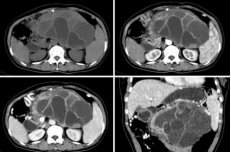

CT表现:平扫呈单发或多发圆形高密度影;肝内胆管结石:常为高密度,呈与肝内胆管走行一致的结节状影,常伴有周围胆道扩张;胆总管结石:多为高密度。结石上部胆管扩张。可见“环靶”征或“半月”征。

MRI表现:与结石成分有关:T2WI,高信号胆囊内可清楚显示低信号结石;胆管结石在T2WIMRCP上呈低信号,MRCP能显示梗阻上方胆管扩张程度,扩张胆管下端呈杯口状充盈缺损。

(3)腺囊性肿瘤:浆液性囊腺瘤常发生在胰腺体尾部,老年女性多见。切面呈蜂窝状;黏液性囊腺瘤和囊腺癌,黏液性囊腺瘤常有恶变的可能,实际上潜在的恶性肿瘤。胰体尾部多见,肿瘤常常很大,为单囊或几个大囊组成。

截屏2022-10-06 19.01.50

胰腺黏液性囊腺瘤

截屏2022-10-06 19.02.15

胰腺浆液性囊腺瘤